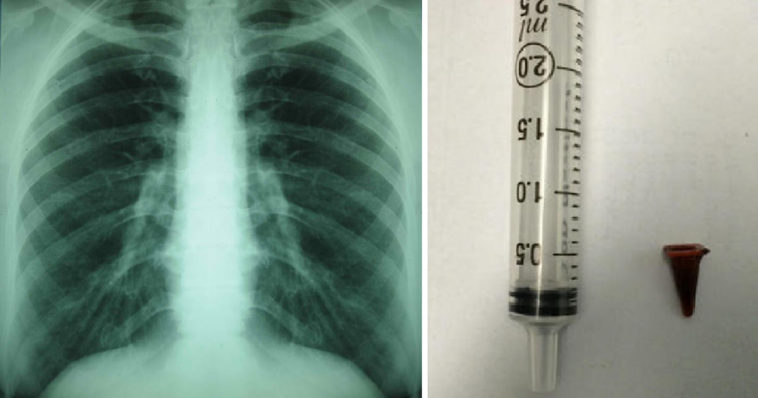

Ωστόσο, όταν έκανε βρογχοσκόπηση, οι γιατροί δεν βρήκαν κανένα σημάδι καρκίνου. Αντίθετα, αυτό που βρήκαν ήταν ένα μικρό παιχνίδι playmobil κολλημένο στους αεραγωγούς του ασθενούς. Αυτό ήταν που προκαλούσε τα καρκινικά συμπτώματα.

Ένας άντρας είχε καταπιεί ένα μικρό παιχνιδάκι playmobil, το οποίο έφραζε τους αεραγωγούς του περισσότερο από 40 χρόνια.

Τελικά, ο άντρας διαγνώστηκε με εισρόφηση ξένου σώματος στο αναπνευστικό σύστημα αντί για καρκίνο. Οι γιατροί ανέφεραν ότι ήταν μια μοναδική περίπτωση και οι πληροφορίες για το περιστατικό δημοσιεύτηκαν στο περιοδικό BMJ Case Reports.

Οι πληροφορίες αναφέρουν, ότι ο ασθενής είχε καταπιεί ένα playmobil από ένα σετ παιχνιδιών που του είχαν κάνει δώρο, όταν ήταν 7 ετών. Καθώς, το μικρό παιχνίδι μπλόκαρε τη δίοδο του αέρα, οι γιατροί προγραμμάτισαν μια επέμβαση για να το αφαιρέσουν.

4 μήνες μετά την εξαγωγή του παιχνιδιού, οι γιατροί ανέφεραν ότι ο βήχας του ασθενούς είχε σχεδόν εξαφανιστεί.